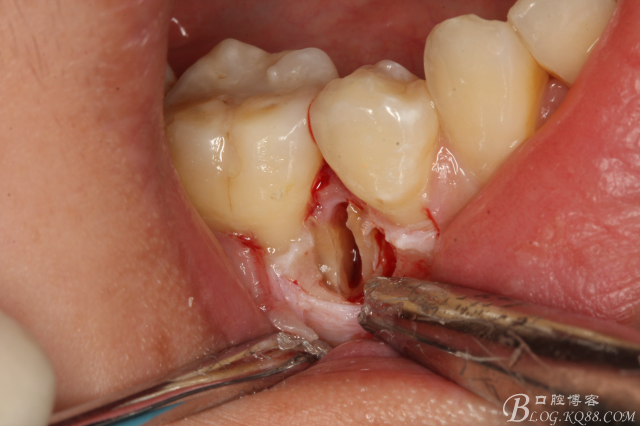

圖11.形成牙根中央一個約5mm長、2mm寬溝槽。

圖12.微創(chuàng)牙挺放入制備好的溝槽內(nèi)。

圖13.取出一塊牙根。給余留 牙根騰出脫位空間

圖14.緩慢在余留牙根周圍用挺,挺松45余留牙根